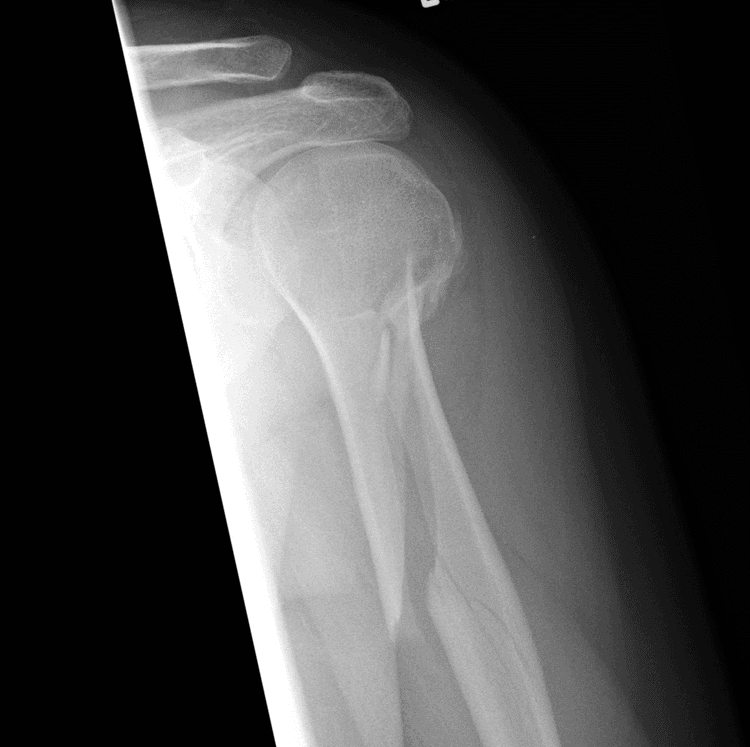

Greenstick Fracture - एका बाजूने फ्रॅक्चर, पण हाड वाकल्याने ते पूर्ण न तुटणे. हे फ्रॅक्चर लहान मुलांमध्ये जास्त आढळून येते कारण त्यांची हाडे लवचिक असतात.